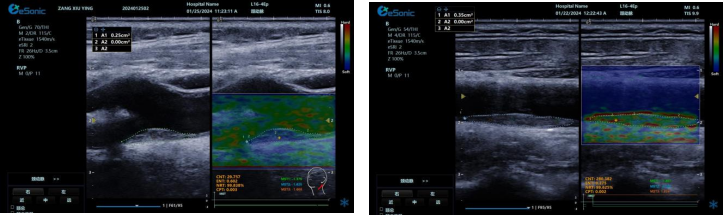

image.png

? 可进行动脉壁运动速度 - 时间彩色成像,直接测量单点脉搏波传导速度及相关参数(如 BSES 时的速度及标准差)。

? 能在血管内中膜增厚前的内皮功能不全阶段检测异常,对早期动脉硬化评估极具临床价值。

? 操作简单直接,无需附加设备,影响因素少,检测快速、重复性和稳定性高。